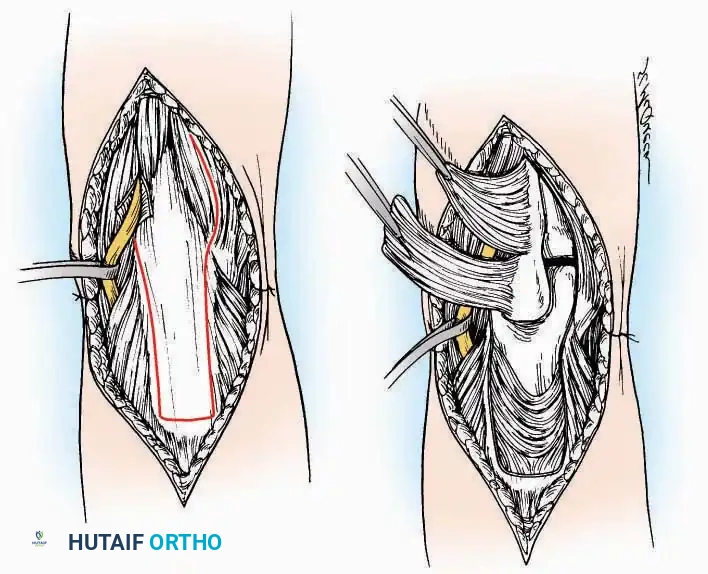

Anterior Approach

Indications: Total ankle arthroplasty (TAA), anterior ankle arthrodesis, and excision of anterior tibial/talar osteophytes (anterior impingement).

Surgical Technique:

* Incision: Make a 10 to 15 cm longitudinal incision over the anterior aspect of the ankle, centered exactly midway between the medial and lateral malleoli.

* Superficial Dissection: Incise the superficial fascia. Identify and protect the superficial peroneal nerve branches laterally and the saphenous nerve medially.

* Internervous Plane: The deep dissection exploits the plane between the Extensor Hallucis Longus (EHL) tendon (innervated by the deep peroneal nerve) and the Extensor Digitorum Longus (EDL) tendons (also innervated by the deep peroneal nerve).

* Neurovascular Bundle: Incise the extensor retinaculum. Carefully identify the anterior tibial artery and the deep peroneal nerve, which typically lie between the EHL and EDL, or directly deep to the EHL. Retract the neurovascular bundle laterally with the EDL, or medially with the EHL, depending on the specific anatomical variant encountered (lateral retraction is most common).

* Capsulotomy: Incise the anterior joint capsule longitudinally. Elevate the capsule subperiosteally from the anterior tibia and the talar neck to expose the entire tibiotalar articulation.